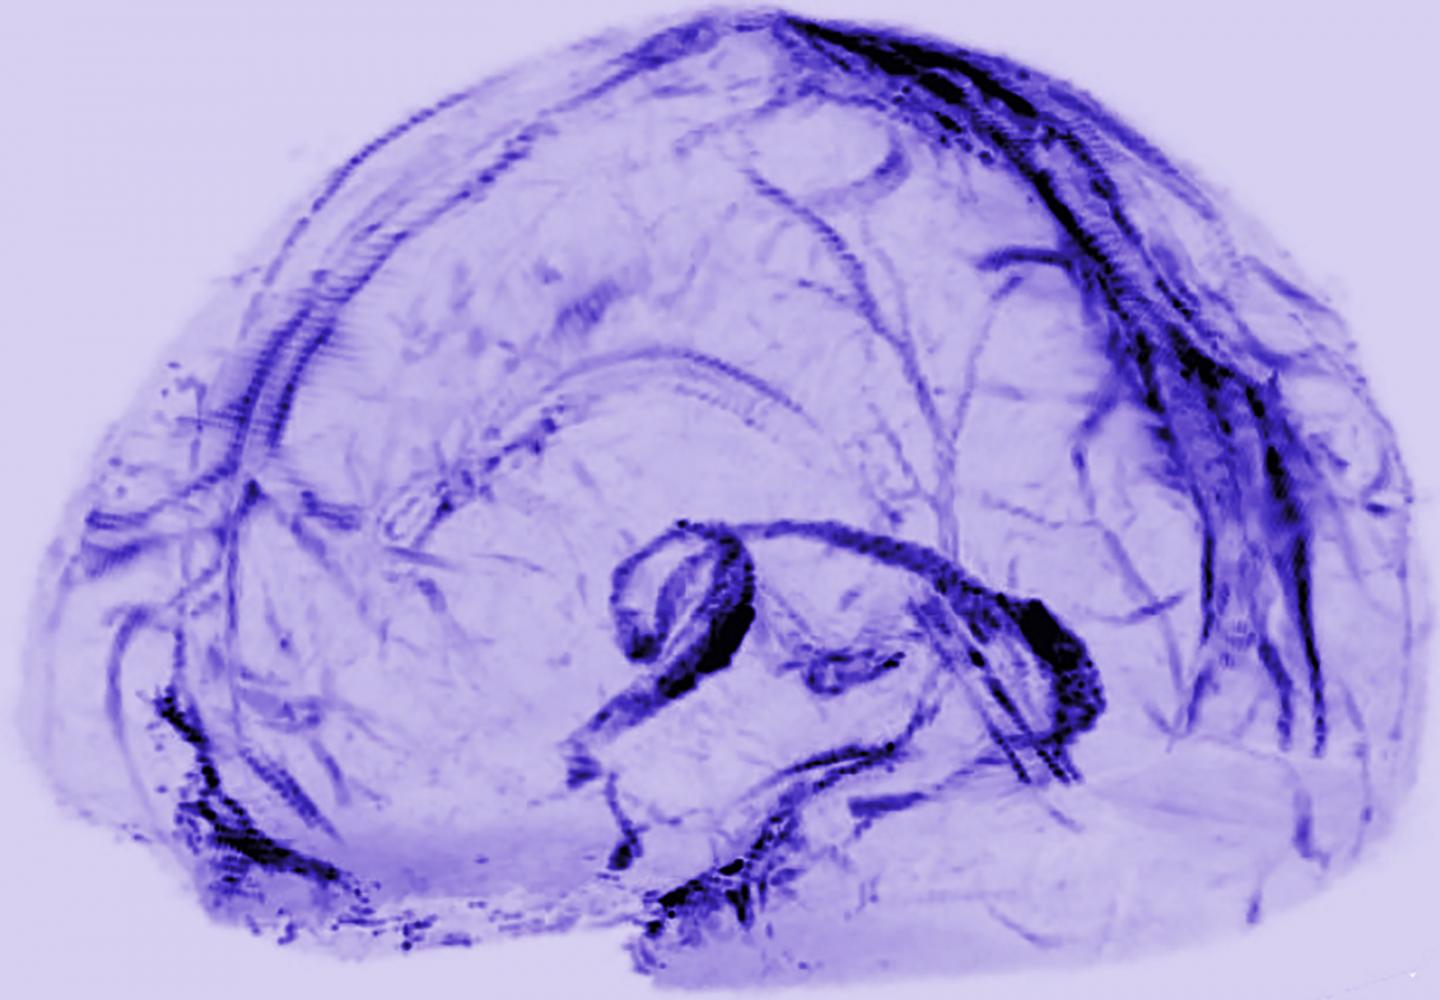

By scanning the brains of healthy volunteers, researchers at the National Institutes of Health saw the first, long-sought evidence that our brains may drain some waste out through lymphatic vessels, the body's sewer system. The results further suggest the vessels could act as a pipeline between the brain and the immune system.

To look for the vessels, Dr. Reich's team used MRI to scan the brains of five healthy volunteers who had been injected with gadobutrol, a magnetic dye typically used to visualize brain blood vessels damaged by diseases, such as multiple sclerosis or cancer. The dye molecules are small enough to leak out of blood vessels in the dura but too big to pass through the blood-brain barrier and enter other parts of the brain.

At first, when the researchers set the MRI to see blood vessels, the dura lit up brightly, and they could not see any signs of the lymphatic system. But, when they tuned the scanner differently, the blood vessels disappeared, and the researchers saw that dura also contained smaller but almost equally bright spots and lines which they suspected were lymph vessels. The results suggested that the dye leaked out of the blood vessels, flowed through the dura and into neighboring lymphatic vessels.

To test this idea, the researchers performed another round of scans on two subjects after first injecting them with a second dye made up of larger molecules that leak much less out of blood vessels. In contrast with the first round of scans, the researchers saw blood vessels in the dura but no lymph vessels regardless of how they tuned the scanner, confirming their suspicions.

They also found evidence for blood and lymph vessels in the dura of autopsied human brain tissue. Moreover, their brain scans and autopsy studies of brains from nonhuman primates confirmed the results seen in humans, suggesting the lymphatic system is a common feature of mammalian brains.